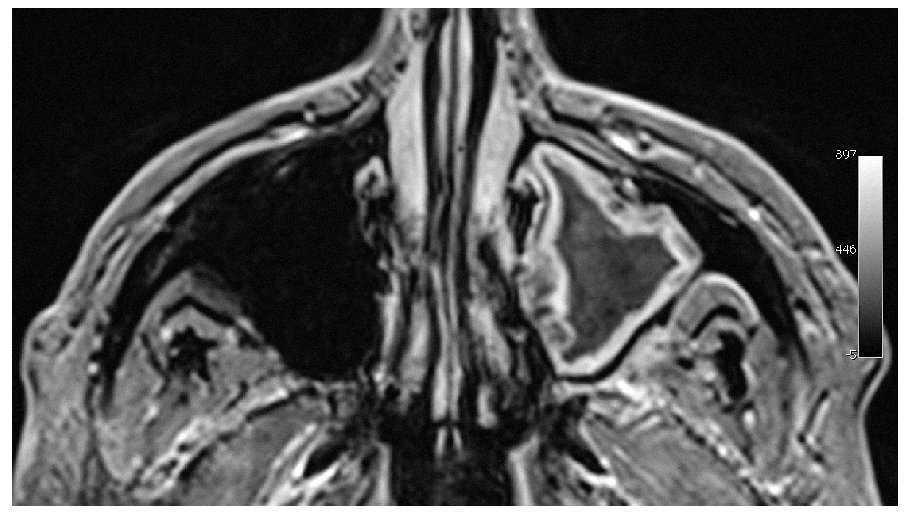

En la tomografía volumétrica digital dental se observa una obstrucción en la zona del orificio fisiológico del seno maxilar izquierdo tanto en el plano axial como en el plano coronal (figs. 1 y 2). El plano coronal permite una comparación excelente con el lado contralateral. Además, en la resonancia magnética se puede distinguir nítidamente la mucosa inflamada y la secreción que ocupa totalmente el seno maxilar (figs. 3 y 4).

Figura 4. Resonancia magnética, plano axial (secuencia T1 con contraste).